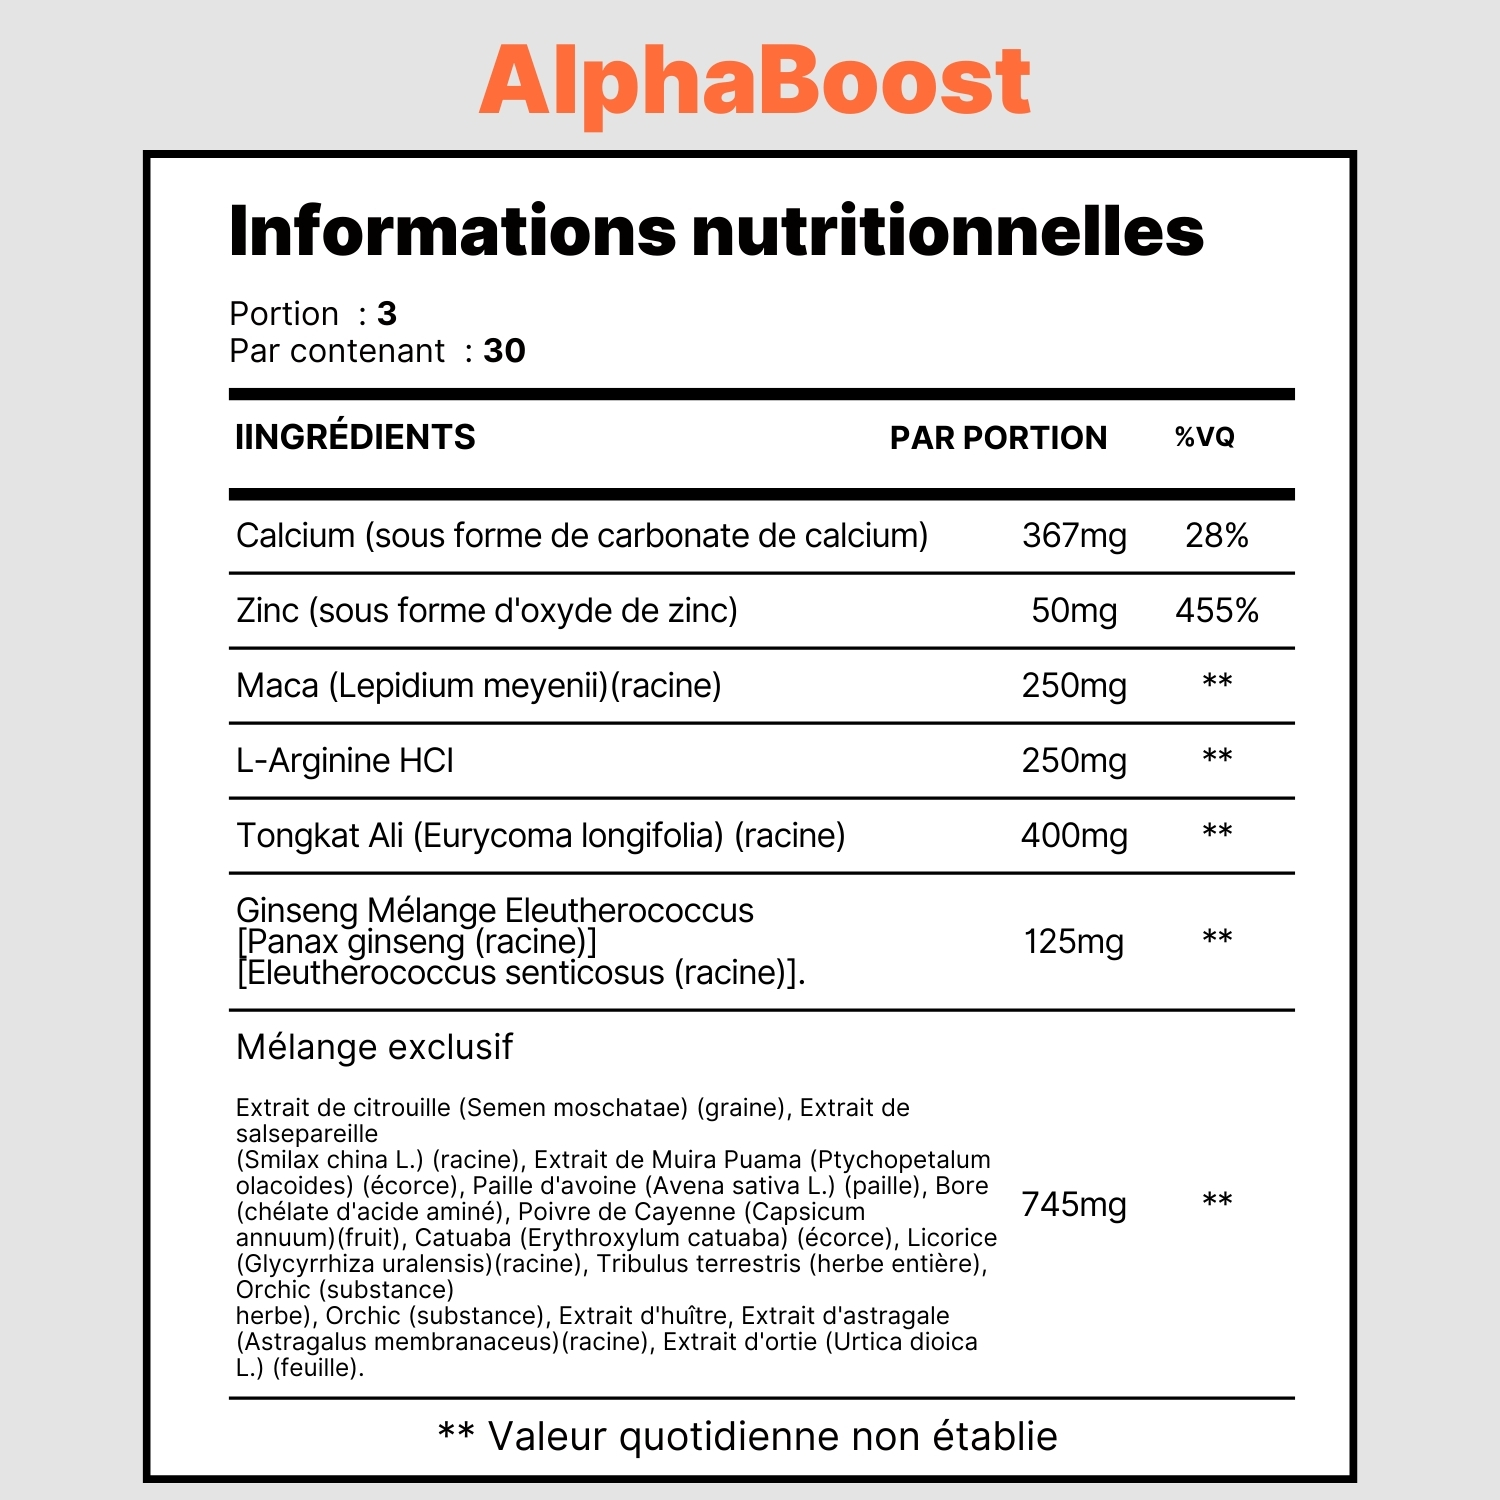

Le supplément AlphaBoost contient un concentré puissant de toutes ces herbes:

Tongkat Ali

Véritable secret de tribus de l’himalaya, il est utilisé depuis des centaines d’années pour réduire le stress oxydatif et favoriser des érections puissantes à tous les âges. Sur une étude menée à Harvard, 75 hommes souffrant de dysfonction érectile ont retrouvé des érections normales après 3 mois de prise du Tongkat Ali.

Ginseng

Un aphrodisiaque réputé qui a aussi un effet sur la circulation sanguine, la réduction de l’inflammation, et le stress oxydatif. En 2017 des chercheurs ont déterminé qu’il s’agit d’un des ingrédients naturels les plus puissants pour lutter contre les troubles de l’érection.

Maca

Dans sa forme la plus concentrée, la poudre de maca est un anti-inflammatoire puissant. Il permet d’améliorer l’afflux sanguin vers le pénis.

Tribulus Terrestris

Il agit directement sur les hormones, contribuant à augmenter le taux de testostérone et faisant augmenter la libido ainsi que la qualité des érections. Les hommes prenant du tribulus durant 45 jours ont jusqu’à 47% plus de testostérone et reportent des érections bien plus fermes.

L-Arginine

Un acide aminé réduisant le stress oxydatif, réduisant l’inflammation et augmentant la circulation sanguine. Dans une étude du Journal of Sex and Marital Therapy, des hommes de 25 à 45 ans souffrant de troubles érectiles ont retrouvé des érections normales.

Suite à ces découvertes en laboratoire, les chercheurs ont décidé de combiner tous ces ingrédients dans un supplément naturel appelé AlphaBoost et de le tester sur des milliers de patients.

AlphaBoost est un complément alimentaire naturel conçu pour améliorer votre vitalité masculine. Il contient des ingrédients puissants qui peuvent stimuler votre métabolisme et votre système hormonal pour vous aider à vous sentir plus énergique et plus confiant.

AlphaBoost contient des ingrédients naturels qui ont été scientifiquement prouvés pour augmenter la production de testostérone, l’hormone masculine clé. L’augmentation de la testostérone peut améliorer votre énergie, votre humeur et votre bien-être général.

Oui, AlphaBoost est un complément alimentaire naturel sûr qui ne contient pas d’ingrédients synthétiques. Cependant, si vous avez des préoccupations spécifiques concernant votre santé, il est toujours recommandé de consulter votre médecin avant de commencer à prendre tout nouveau supplément.

Les résultats peuvent varier d’une personne à l’autre, mais la plupart des gens commencent à remarquer les effets positifs d’AlphaBoost dans les deux à trois semaines suivant la prise du complément. Il est important de noter que l’utilisation régulière d’AlphaBoost peut fournir des résultats plus durables et plus significatifs.

Il est recommandé de prendre deux capsules d’AlphaBoost par jour, de préférence avec un repas. Il est important de respecter la posologie recommandée et de ne pas dépasser la dose maximale recommandée.